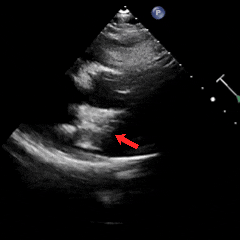

术后1月随访

术后1月随访,患者自述症状较前明显减轻,复查心脏彩超提示可降解封堵器形态位置良好,无残余分流,周围其他结构无异常。